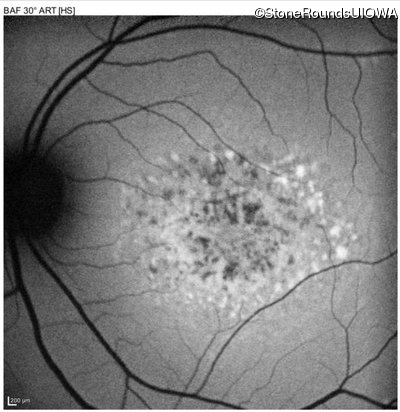

Blue Autofluorescence - Right - 10/125 -1

Exemplar